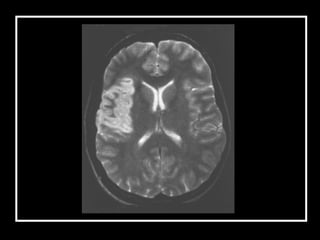

Anamnese Exame físico Exames de imagem Diagnóstico

Anamnese Exame físicoExames de imagem Diagnóstico